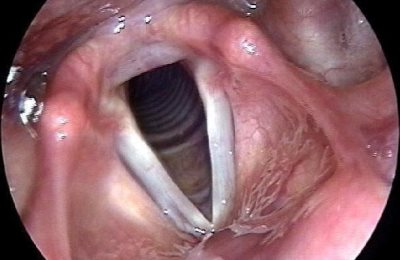

При осмотре выявляется резкое покраснение слизистой оболочки гортани. Также могут быть заметны дифтерийный налет или булезное утолщение слизистой при туберкулезе. При обычном, катаральном ларингите, вызванном вирусами, специфических изменений в слизистой оболочке нет.

Ларингит – это воспаление гортани, как правило, являющееся следствием вирусной инфекции. Это приводит к резкому изменению голоса, появляется слабость голоса и осиплость. Диагноз ставится на основании клинических проявлений. При проявлении симптомов более 3 недель необходимо выполнить ларингоскопию.